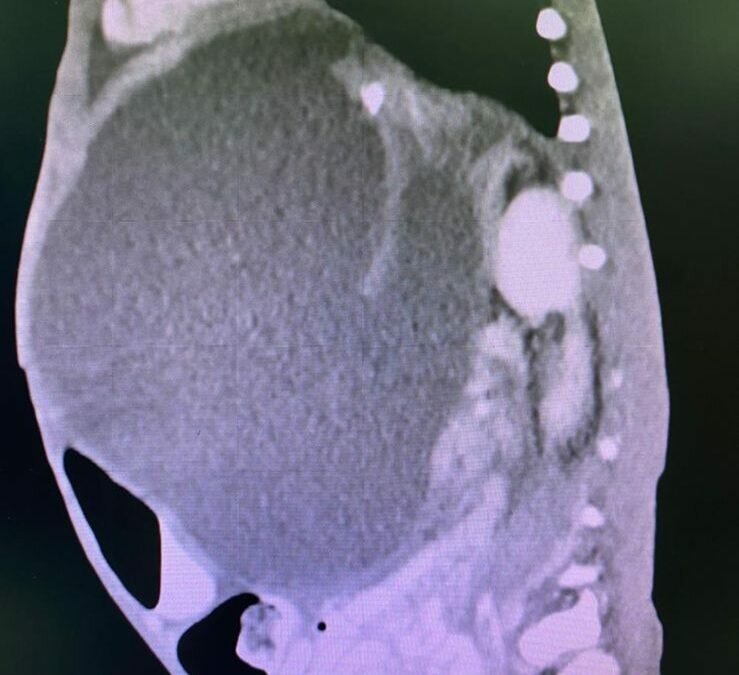

وفور وصول الحالة أجرى الأطباء الفحوصات الطبية اللازمة وتبين انه يعاني من التهاب في البنكرياس مع وجود تكيس كبير الحجم، وتم وضع الخطة العلاجية من خلال الفريق الجراحي بقيادة الدكتور / تركي رشاد وفريق الجهاز الهضمي بقيادة الدكتور / احمد المحمادي.

وتم إزالة التكيس المتضخم وذلك بعمل شق جراحي في المعدة والدخول الى التكيس وازالة ما بداخله وعمل توصيلة ما بين التكيس والمعدة للاستفادة من انزيمات البنكرياس و تكللت العملية بالنجاح والطفل في حالة صحية مستقرة ولله الحمد.